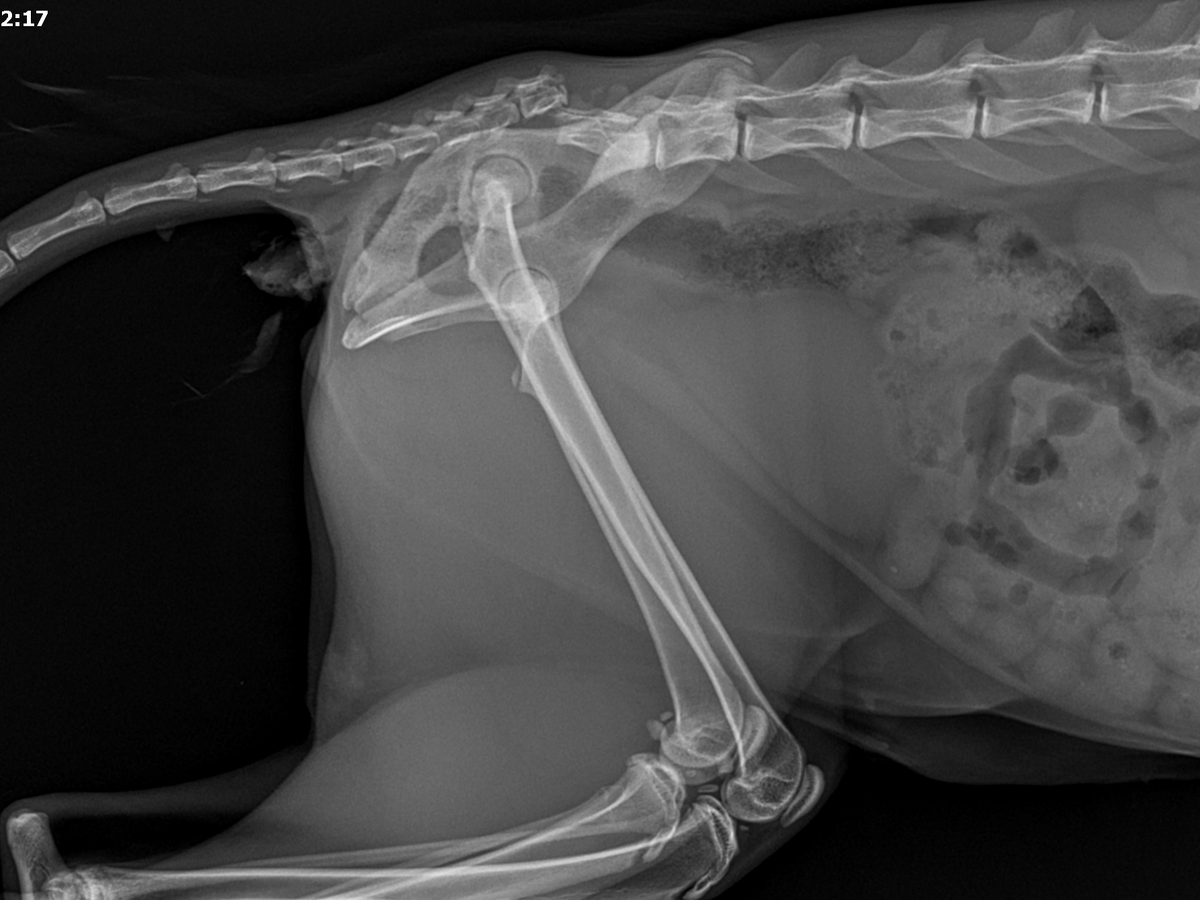

During her visit to Furry Friends, the vet noticed that Zombie reacted strongly when touched near her back end, shifting quickly from calm to distressed. She held her tail awkwardly and walked as though in pain, indicating possible trauma in that area, which had not been mentioned by JPaws. She has never been X-rayed, so these issues had gone undetected before we brought her home.

Since then, Zombie has been to two separate veterinarians. The team at Furry Friends was wonderful and helped stabilize her, but they suspected she might need a tail amputation. They unfortunately lost X-ray capabilities, and Zombie was in too much pain to be examined without sedation, so we took her to Acadiana West Animal Clinic for further evaluation.

Today, November 6th, we received confirmation that Zombie does indeed need a full tail amputation. Despite all she’s endured, she remains the sweetest, most trusting cat, and every vet who’s met her has fallen in love with her gentle spirit.